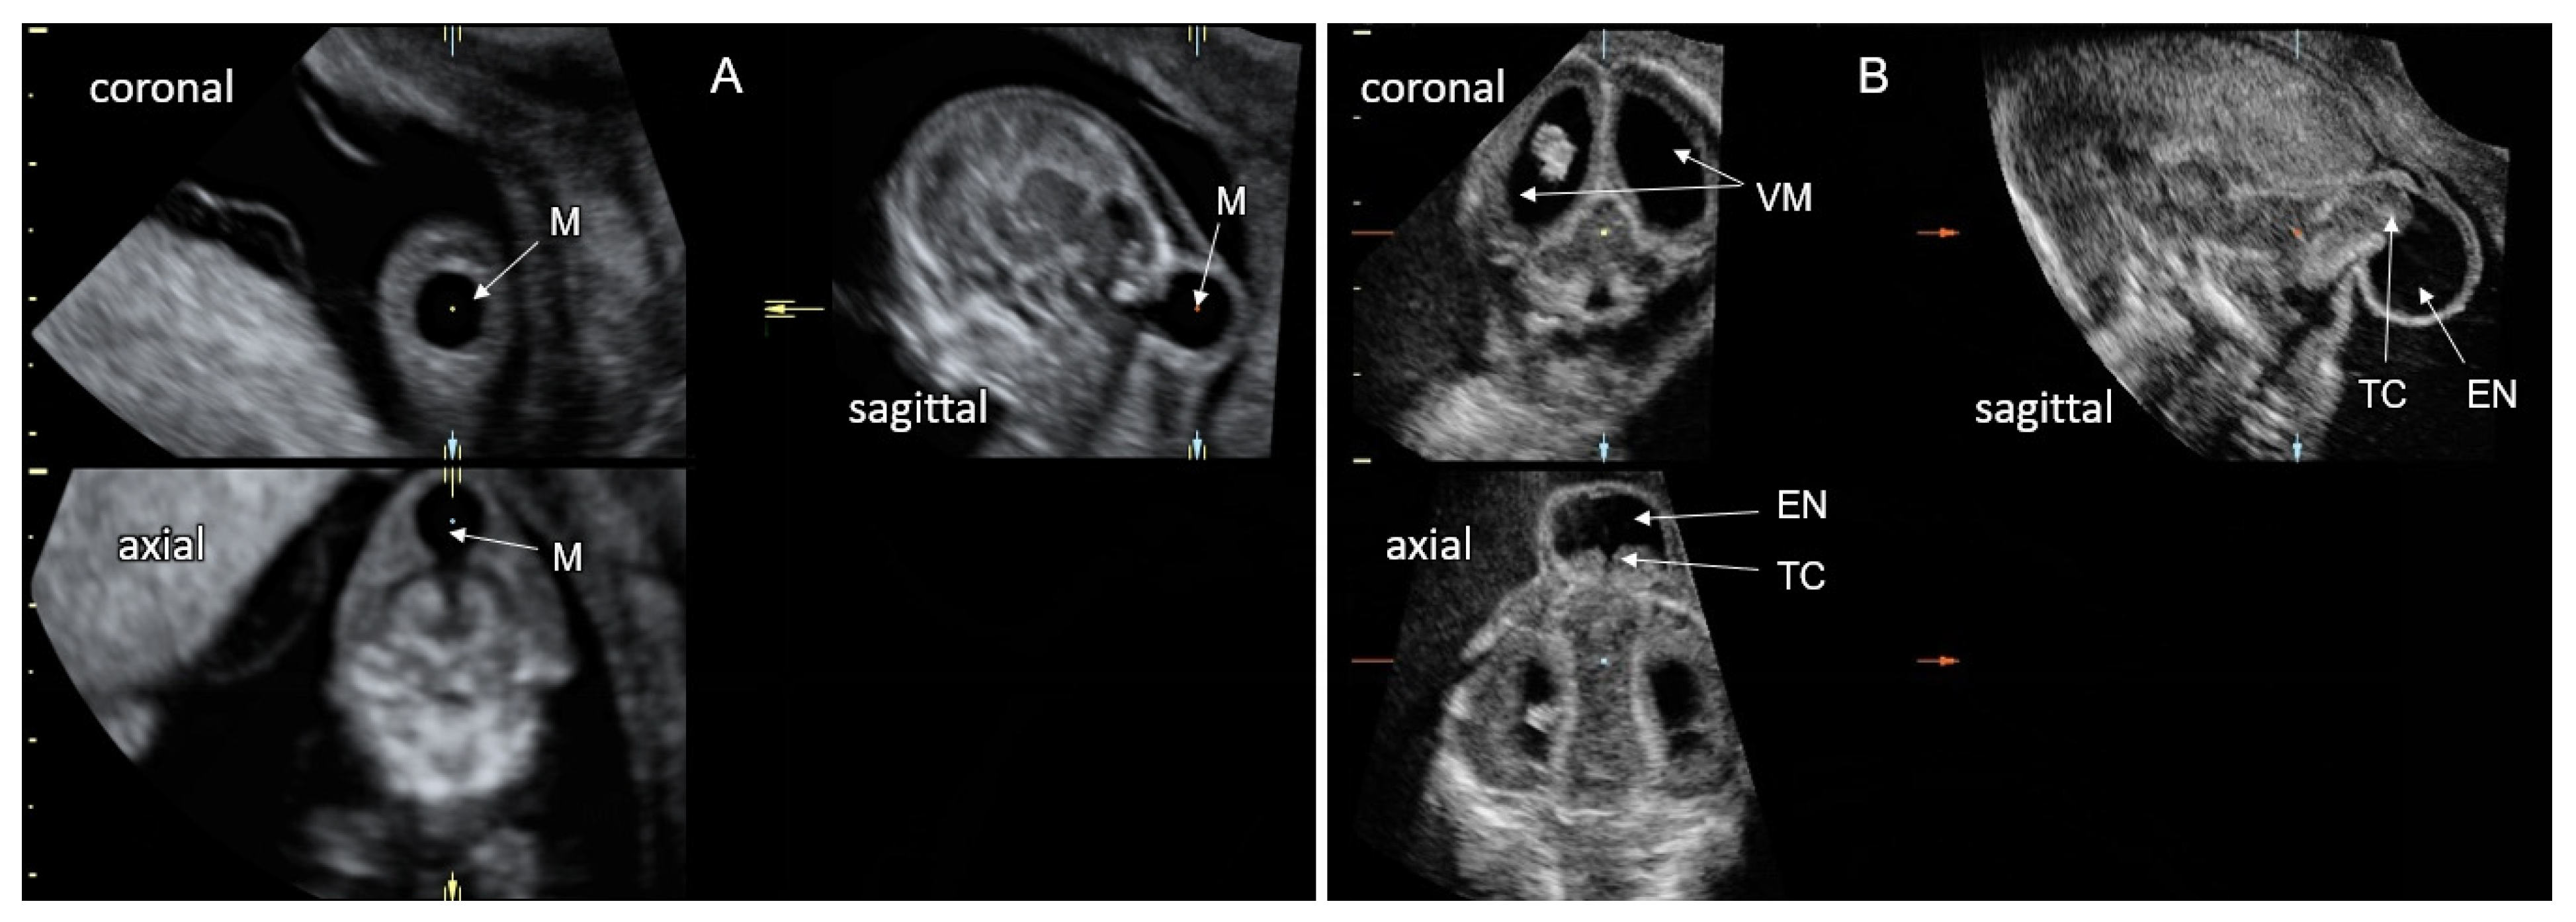

8. Ventriculomegaly